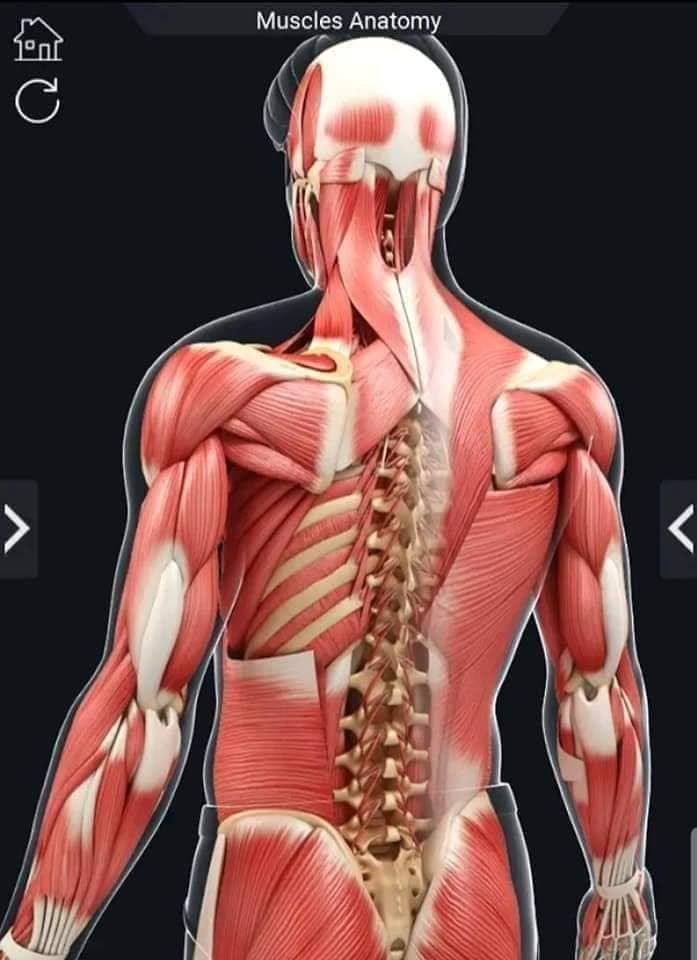

М'язова система людини є однією з основних систем організму, що відповідає за рухи, підтримання пози та стабільність. Вона складається з понад 600 м'язів, які можна класифікувати на скелетні, гладкі та серцеві м'язи. Скелетні м'язи, які є об'єктом нашого детального розгляду, дозволяють контролювати навколишній світ і виконувати різноманітні рухи. Особливу увагу в нашій статті буде приділено шейним і спинним м'язам, оскільки ці групи м'язів мають критичне значення для підтримання правильного постава та функціонування хребта.

Спинні м'язи

Спинні м'язи виконують функції підтримки хребта, а також дозволяють здійснювати рухи тулуба.

Поверхневі спинні м'язи

М'язи, що піднімають лопатку: Трапецієподібний м'яз: великий м'яз, що покриває верхню частину спини. Його функція - підтримка і рух лопаток, а також забезпечення стабільності хребта.

М'язи, що ведуть лопатку до хребта: Широкий м'яз спини: великий м'яз, що розташований в нижній частині спини. Він відповідає за рухи плечей і лопаток, а також за розширення верхньої частини тулуба.

Глибинні спинні м'язи

М'язи, що забезпечують стабільність хребта: М'язи, що розташовані між хребцями: включають мускулатуру, яка забезпечує стабільність і підтримку хребта, а також дозволяє здійснювати рухи хребта.

М'язи, що здійснюють ротацію та нахили

М'язи, що забезпечують ротацію хребта: Ротаційні м'язи: допомагають у здійсненні обертальних рухів тулуба, а також у підтримці рівноваги і стабільності хребта.